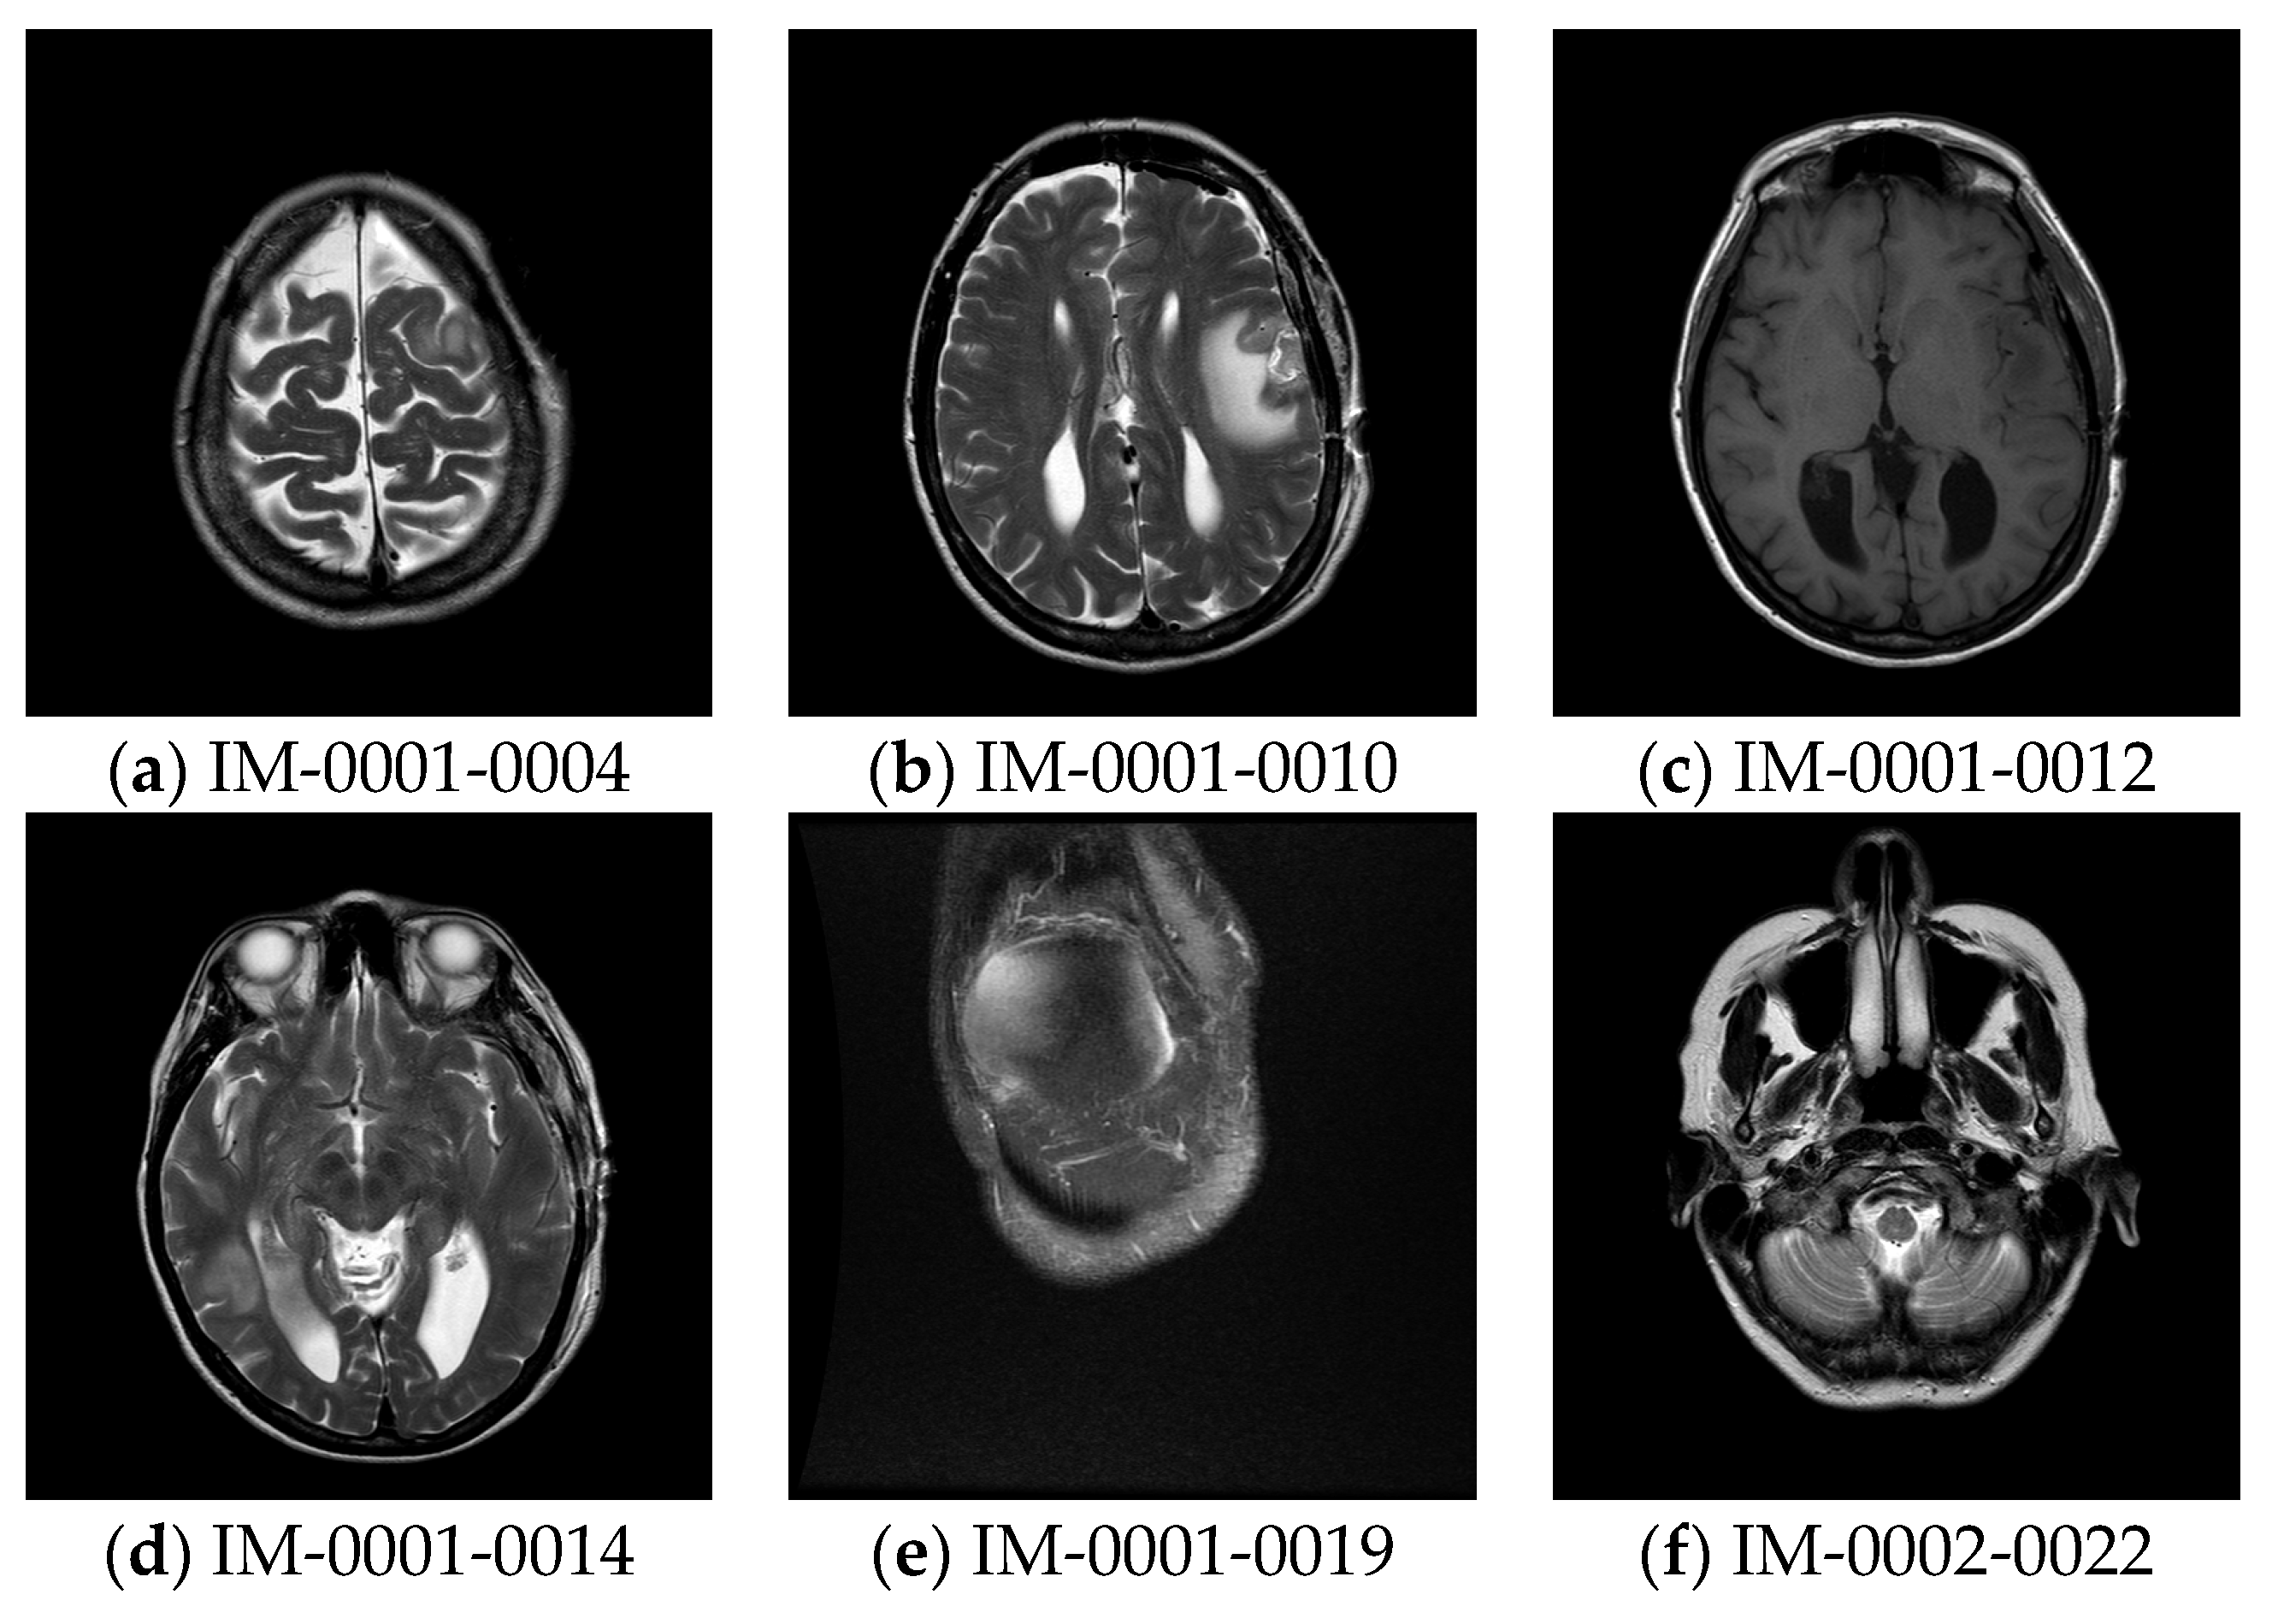

The experiment was conducted by MATLAB version 12b. The 256-grey scale test images with the size of 512 × 512 are given in Figure 5.

Figure 5. Test images.

Preprints 80000 g005